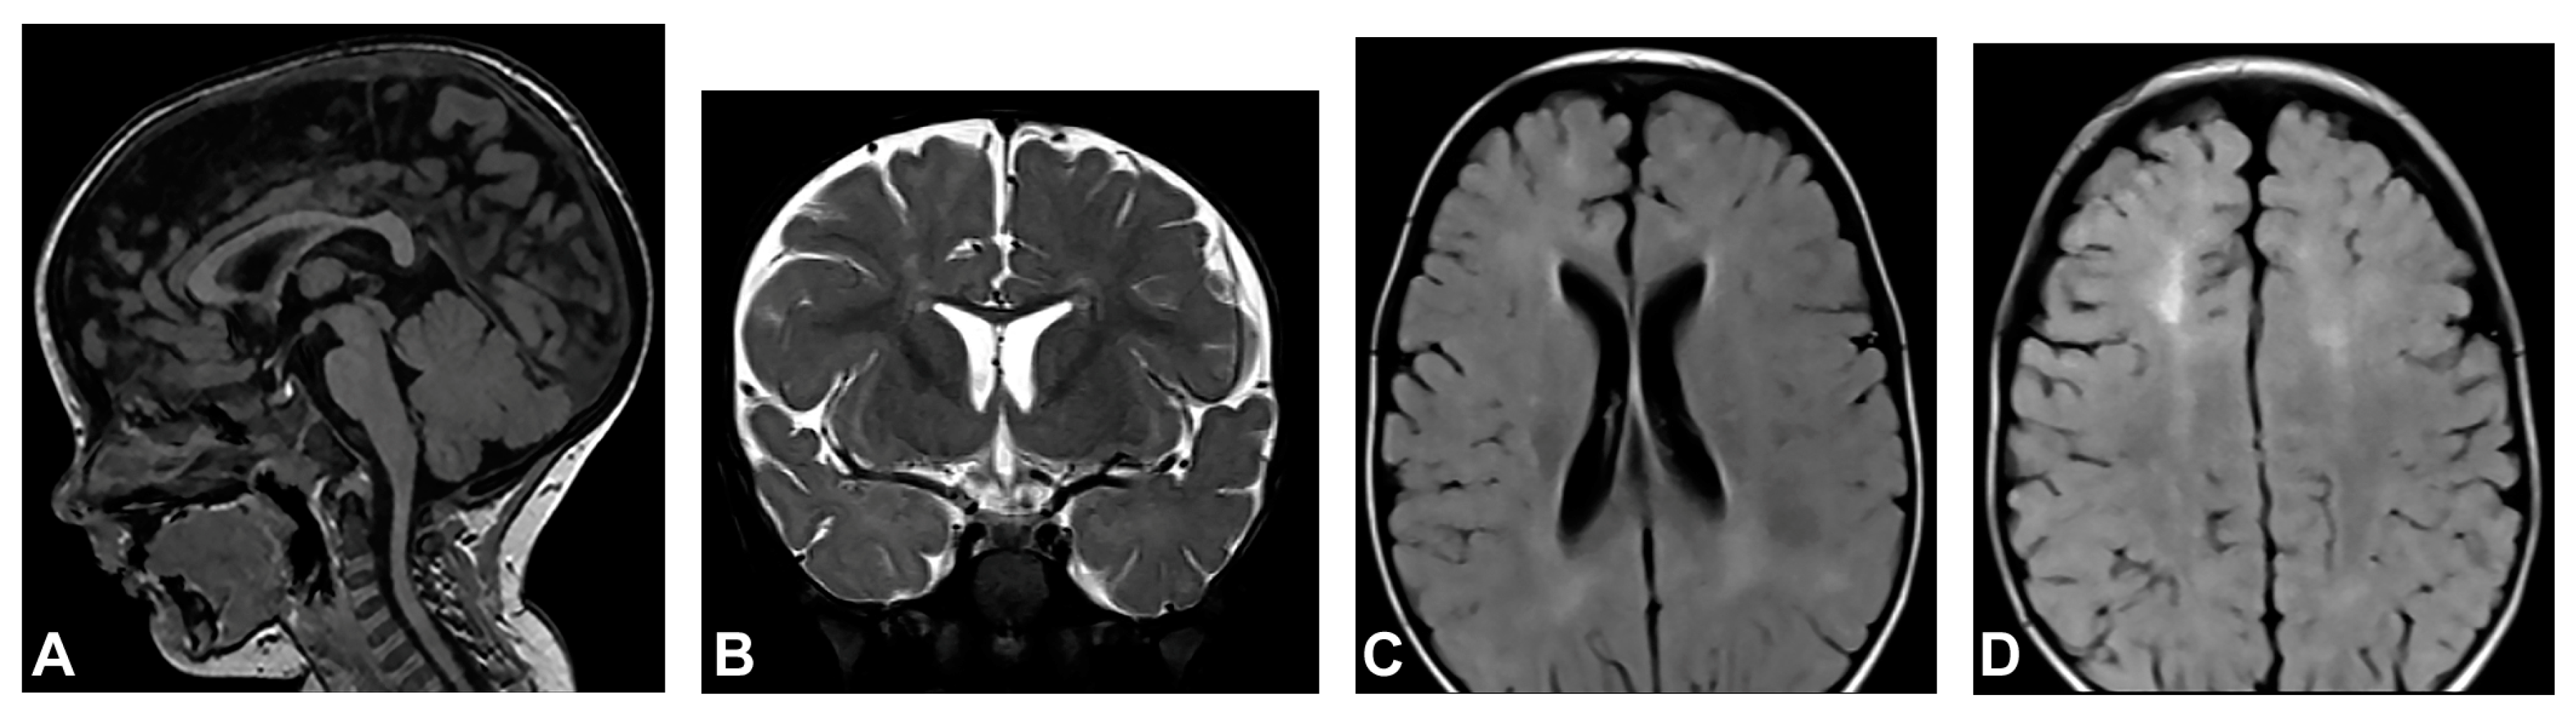

Skin changes were visible upon birth that evolved from stage I to stages III and IV of IP. Neonatal convulsions occurred immediately after birth. Skin biopsy was performed, and IP was histopathologically confirmed in both the patient and her mother. IKBKG exon 4–10 deletion was genetically confirmed in the patient’s mother as well. The patient presented dental and oral anomalies such as peg-like teeth, delayed eruption, and gothic palate. Ophthalmological examination revealed strabismus. The patient was severely delayed in terms of psychomotor development, partially due to spasticity. She started to walk independently from the age of five and a half but without a normal walking pattern. Neurological examination revealed microcephaly, spastic quadriparesis more severe on the right side, intellectual disability and prominent speech delay. Physical and speech rehabilitation were performed every day. She had focal epileptic seizures from the age of one and a half, and EEG recording showed focal epileptic activity. Antiepileptic therapy was given (valproate), and good control of seizures was achieved. MRI of the brain showed microcephaly and brain atrophy with atrophy of the thalamus and the basal ganglia (Figure 2). Supratentorial white matter loss was observed with an increased signal on T2W/FLAIR and mildly enlarged lateral ventricles, more evident on the left side. In addition, it revealed a marked hypoplasia of the CC, especially of the rostrum and body.

Figure 2.

(Case 2) (A) Sagittal T2W magnetic resonance image at the age of one shows CC hypoplasia especially of the rostrum and body. (B) Axial T2W magnetic resonance image shows brain atrophy, supratentorial white matter reduction with elevated IS on T2W/FLAIR and gliotic changes. Mild bilateral non-progressive ventriculomegaly is more prominent on the left.